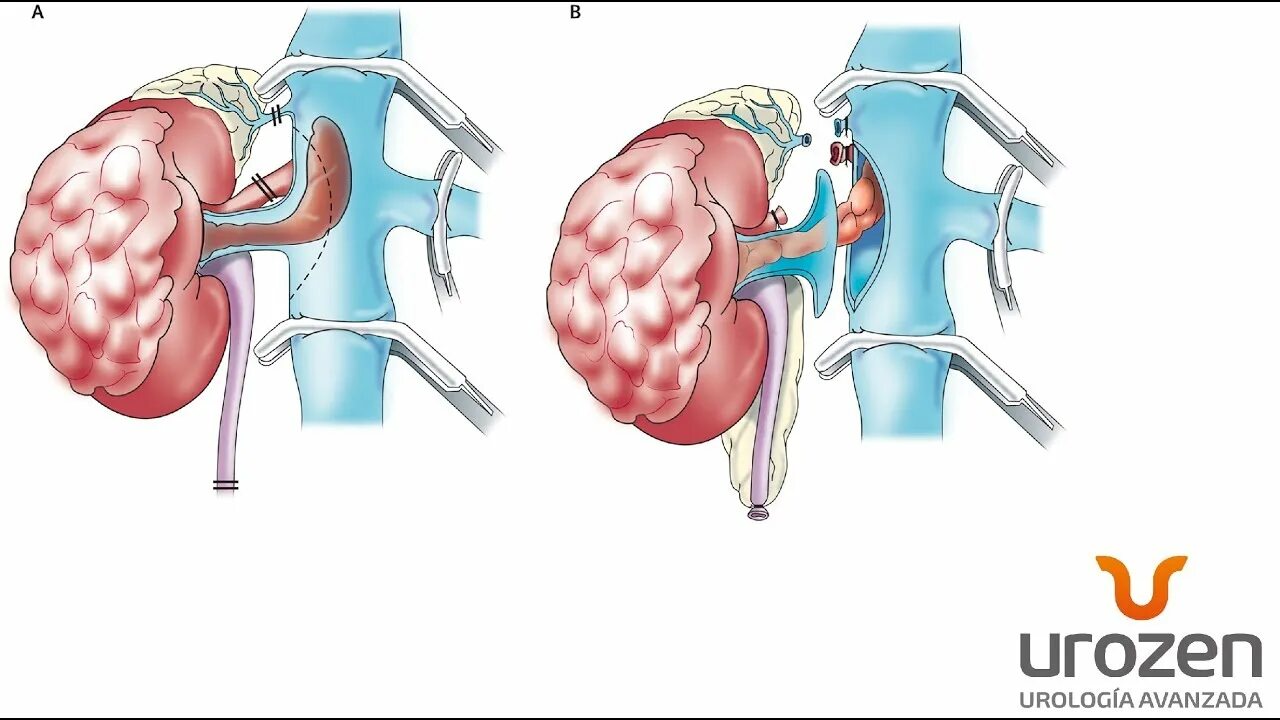

Гидронефроз почки после операции